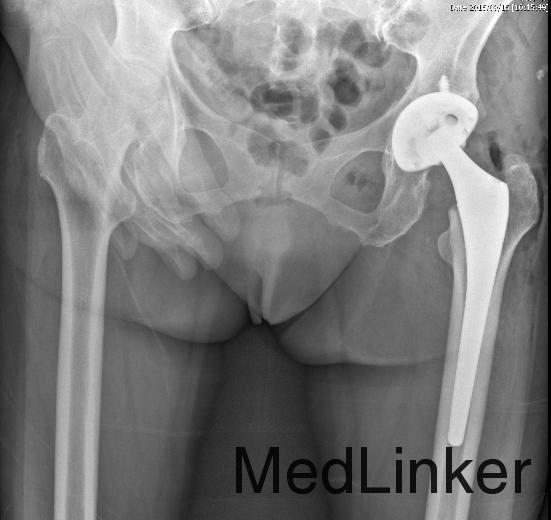

诊断:左髋置换术后髋关节脱位; 治疗:急诊行髋关节复位术。

术后患者恢复良好,疼痛明显减轻,左髋畸形矫正,卧床穿丁字鞋维持髋关节中立位,复位后五天患者顺利出院,未再发生脱位。